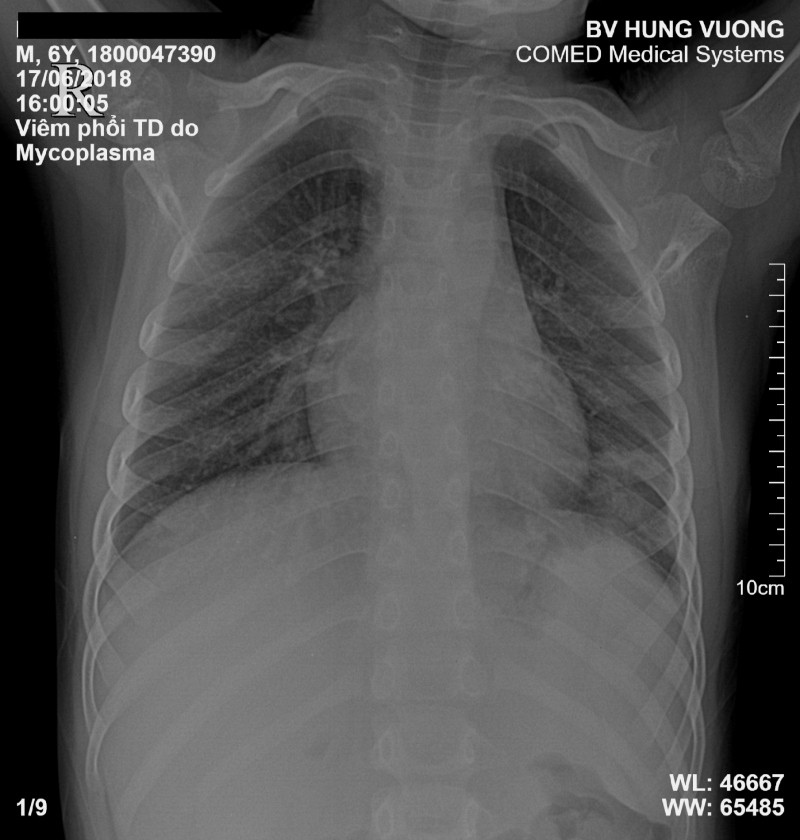

2.1. Viêm phổi do vi khuẩn Mycoplasma gây ra

Đây là một bệnh nhiễm trùng phổ biến do vi khuẩn Mycoplasma pneumoniae gây ra. Các triệu chứng thường gặp của bệnh không giống như bệnh viêm phổi thông thường. Cụ thể như sau:

Viêm phổi do Mycoplasma cần điều trị sớm để tránh nguy hiểm